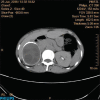

Echinococcosis is a parasitic infection caused by the larval stage of a cestode Echinococcus granulosus and is endemic in sheep farming regions of developing countries. It manifests as hydatid cyst and most commonly is found in liver followed by lungs. Renal hydatid cyst is rare and amounts for 2% of all cases. There are no specific clinical manifestations, and hence diagnosis of renal hydatid disease is missed out easily without imaging. We report a case of 50-year-old female who had 6 months history of lower abdominal pain with hematuria, found to have right renal hydatid cyst on imaging which was treated with right nephrectomy with pre- and post-operative albendazole treatment.